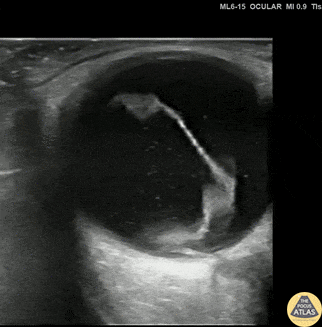

Orbital - Spontaneous Retinal Detachment

30s M with no known medical history or ocular history presented with 2 days of progressive monocular visual field deficits and floaters without antecedent trauma or other injury. Visual acuity was limited to finger counting at 3 feet in the affected eye. POCUS of the affected eye is shown here, demonstrating a macula-off retinal detachment. The patient was seen by ophthalmology and had urgent surgery the next morning. Dr. Amy Allen, PGY1 Denver Health Residency in Emergency Medicine